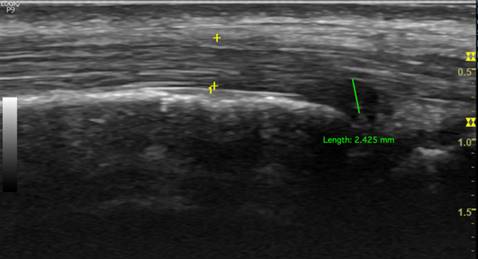

Figure 3

Longitudinal sonographic of posterior tibialis tendon with partial tear.

Ultrasonography

PTT is well-assessed using US. We used a GE Logiq P9 ultrasound machine with an 18 MHz linear array transducer to scan the PTT. The position of the transducer in the PTT for ultrasound scanning is essential for obtaining accurate results. The subjects were placed in the lateral decubitus position. The PTT was scanned in longitudinal and transverse positions (Figure 1). Posterior tibialis dysfunction appears as tenosynovitis, tears, or tendinosis. The free fluid collection that created a hypoechoic lesion around the PTT and a sheath size greater than 7mm was tenosynovitis (hyperechoic central structure with a hypoechoic halo) on the ultrasound transverse position (Figure 2).[5, 22] A PTT tear or rupture appeared on ultrasound as an empty tibial groove with an intermuscular gap in the PTT (Figure 3). Tendinosis results in posterior tibial tendon thickening, with heterogeneous hypoechoic regions replacing the normal fibrillar architecture.[20]